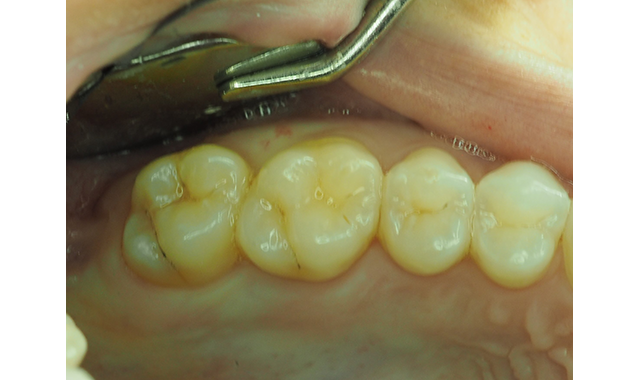

Fig. 1 The pre-operative view, with deep pit caries in newly erupted maxillary second molar.

Consequently, the patient still had carious maxillary second molars to be restored (Fig. 1). She was concerned the restorations would be “painful” postoperatively and worried about the consequences of the planned posterior composite restorations.